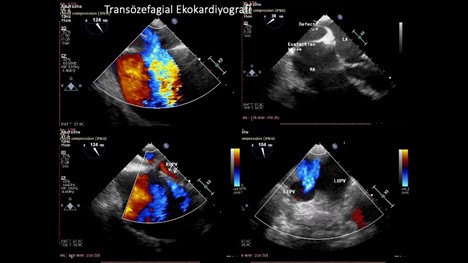

Yapılan TEE değerlendirmede; soldan sağa tek yönlü geçiş gösteren inferior tip sinus venosus ASD görüntülendi. Pulmoner venlerin değerlendirilmesinde ise sol pulmoner venler ve sağ üst pulmoner venin sol atriyuma döküldüğü gözlemlenirken sağ alt pulmoner ven gösterilemedi (Resim-6).

Resim-6: